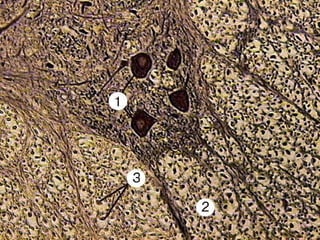

Coarnele ventrale sunt formate din neuroni motori şi neuroni de

asociaţie.

Neuronii motori sunt reprezentaţi de:

a) neuroni alfa-motori (descrişi mai jos) care inervează fibrele

musculare striate scheletale

b) neuroni gama-motori, care se distribuie fibrelor musculare din fusul

neuro-muscular.

Coarnele dorsale prezintă în structura lor neuroni de

asociaţie, cu semnificaţia neuronilor senzitivi de ordinul II.

Dendritele lor fac sinapsă cu axonii neuronilor din ganglionii

spinali (neuroni de ordinul I).